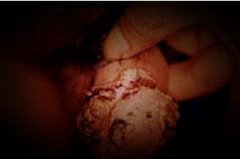

石家庄九州皮肤病医院 > 尖锐湿疣 > > > 哪些生活细节会引起尖锐湿疣发病复发呢?尖锐湿疣无论是在生活当中还是在临床上都是可以给患者造成很大影响伤害的,因为尖锐湿疣对患者所造成的精神影响和伤害是很严重的。而得了尖锐湿疣的患者患者应当去及时的治愈才行。现在对于尖锐湿疣的治疗有很多物理的方法,包括冷冻、激光、微波和光动力等等,这些方法是可以很快帮助患者去消除症状的,但是却未必能够彻底的清除尖锐湿疣病毒,所以复发还是存在着几率的。